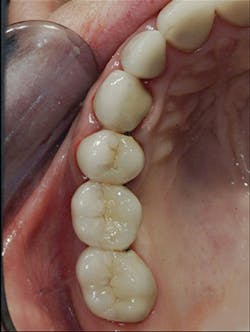

5. All tooth structure gone to the bone. Endodontic treatment. Post and core placed. Not enough tooth structure to provide a ferrule. Nonabusive occlusion (Figures 3 and 4)-Orthodontic tooth extrusion is a technique seldom used in dentistry, but it can possibly save such teeth. In spite of being taught to dental students, I find in my CE courses that orthodontic tooth extrusion is seldom accomplished. If the tooth root is long, the technique can be successful. Additional cost to the patient is necessary, accompanied by the time for orthodontic tooth movement, and a period of bone stabilization before restoring the tooth. Crown lengthening is another option if such treatment will not cause an esthetic challenge. Presence of abusive occlusion adds a strong negative to this clinical situation. Most dentists do not accomplish orthodontic extrusion or bony crown lengthening. Therefore, removal of the tooth and placement of an implant remain as the most predictable and viable solution.